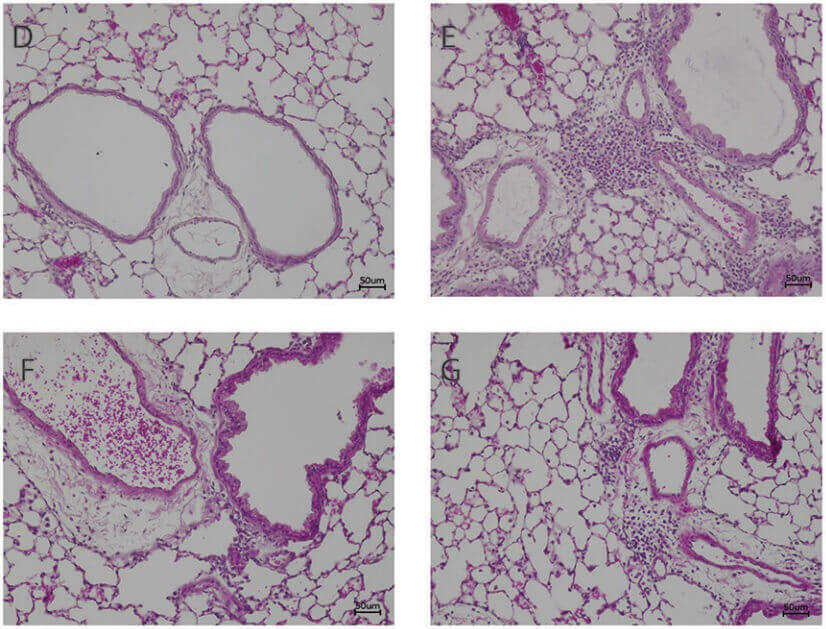

Fig. 1 Photomicrographs of the lungs of HDM-allergic mice stained with H&E. 1

- Verheijden, Kim AT, et al. "The combination therapy of dietary galacto-oligosaccharides with budesonide reduces pulmonary Th2 driving mediators and mast cell degranulation in a murine model of house dust mite induced asthma." Frontiers in Immunology 9 (2018): 2419. Distributed under Open Access license CC BY 4.0. The image was modified by extracting and using D-G part of the original image.